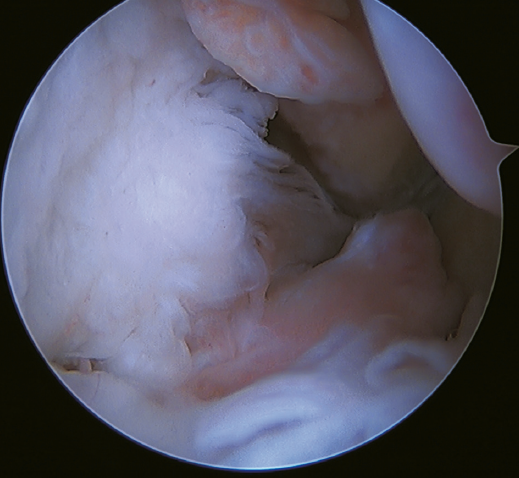

A recent consensus(64) recommends reconstruction of the ATFL and CFL (Figures 5 and 6) in cases of generalized laxity or when there is poor tissue quality. Other indications would be when there are doubts about subtalar stability or in patients with a ruptured CFL. For some authors, BMI > 30 kg/m2 would also be an indication for this technique.

Figure 5. Tearing of the anterior talofibular ligament and calcaneofibular ligament with poor tissue quality of the ligament remnant.

Figure 6. Arthroscopic view of a dual allograft reconstruction of the anterior talofibular ligament (1) and the calcaneofibular ligament (2), showing correct tension and positioning of the fascicles.